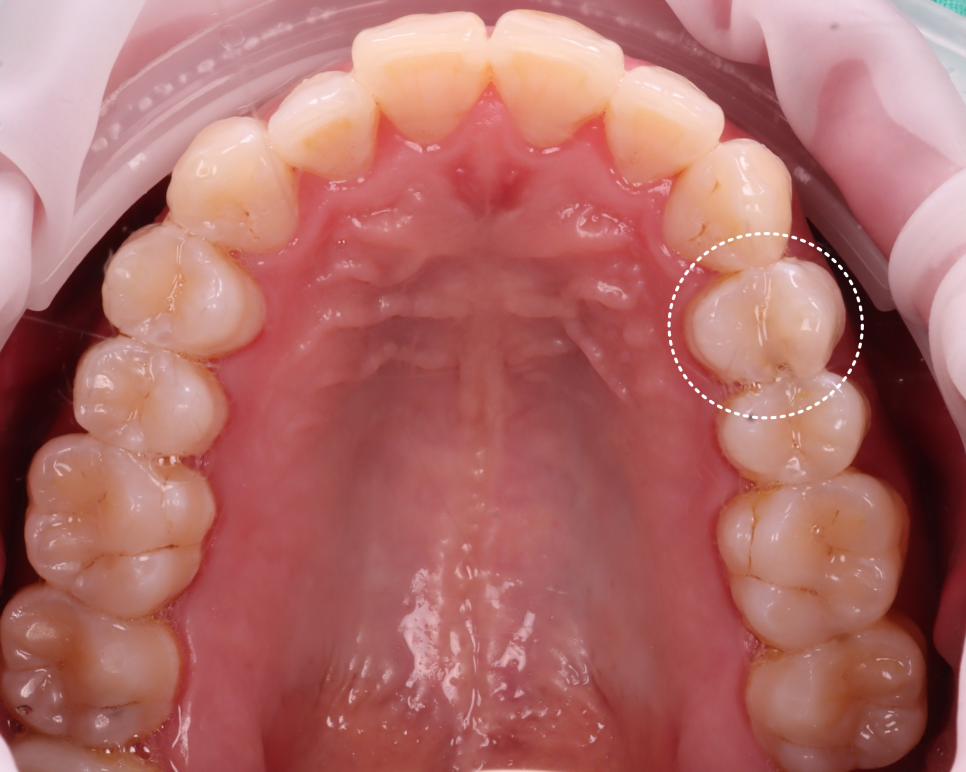

오늘 소개해 드릴 분은 40세 남성분으로 3년 전에 다른 치과에서 레진으로 치료했던 곳이 한 달 전쯤 깨지면서 떨어졌다고 하셨어요.

내원 당시 치아는 겉보기엔 멀쩡했지만 기존 레진이 떨어져 그 아래로 세균이 침투한 흔적이 있었어요.

촬영일 : 251020

이를 2차 충치라고 부르는데 적절히 치료되지 못한 경우에 접착이 깨지고 그 틈으로 세균이 침투해서 다시 충치가 생길 수 있어요.

생각보다 파절 부위가 커서 걱정이 됐는데요.